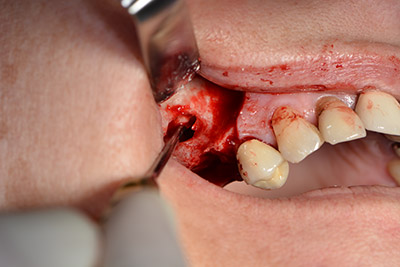

Procedimiento quirúrgico durante el implante

fresado piloto

Imagen 9: Visión global y ajuste para el fresado piloto.

El guiado clásico del corte (crestal, descarga bucal) y la preparación del colgajo mucoperióstico permiten obtener una buena visión global.

En este caso se utilizan implantes Sky (Bredent), cuyo protocolo quirúrgico exige el fresado piloto a unas 1.200 rpm (figura 9).